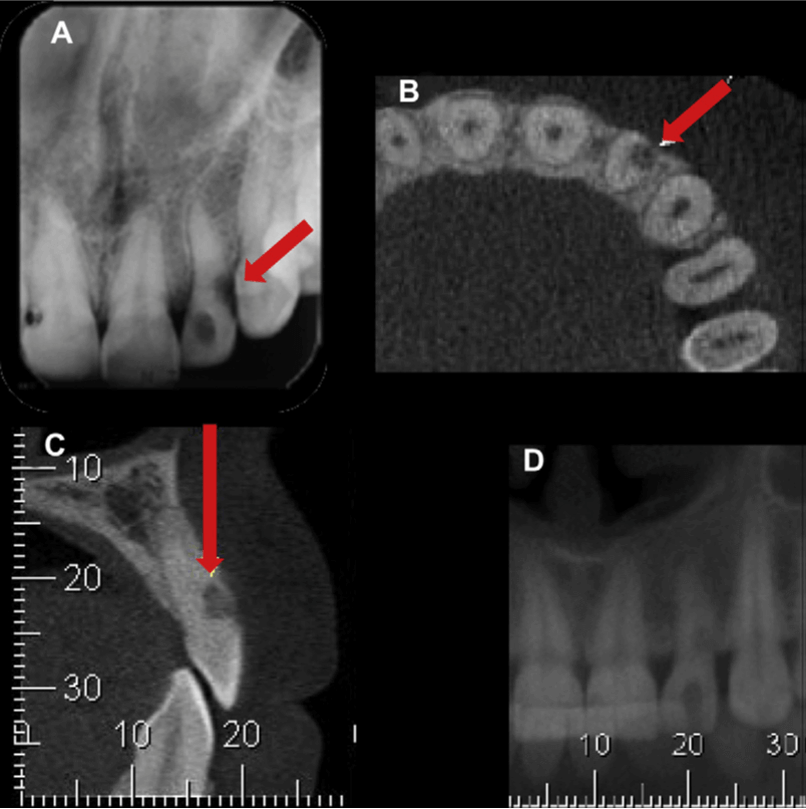

Sin embargo, la reabsorción radicular inflamatorio es una lesión asintomática, lo cual hace más complejo su diagnóstico y tratamiento. El criterio estándar para el diagnóstico de este tipo de reabsorción se da por medio del análisis microscópico. Las imágenes radiográficas convencionales se han utilizado con frecuencia para la detección y seguimiento de la reabsorción radicular inflamatoria. Sin embargo, el acortamiento apical, los defectos dentarios radiculares laterales o cervicales, el agrandamiento del conducto radicular y los defectos radiolúcidos radiculares externos no es posible identificarlos en una evaluación radiográfica en su fase inicial cuando el proceso de reabsorción inflamatoria es discreto, o debido a las limitaciones de las radiografías convencionales conocidas como la distorsión geométrica o la superposición.

La tomografía computariza cone beam ofrece múltiples ventajas que pueden influir de forma considerable en las decisiones tomadas por los odontólogos para la elaboración de un plan de tratamiento. La detección precoz de la reabsorción radicular inflamatoria puede conducir a una intervención oportuna y a mejores resultados del tratamiento. Por medio de la tomografía computarizada cone beam se puede evaluar la extensión real de la reabsorción radicular inflamatoria analizando todas las dimensiones de la lesión mediante la evaluación de los cortes axiales, coronales y sagitales. Además, se pueden realizar mediciones del tamaño de los defectos radiculares como parte de un seguimiento longitudinal, lo cual es útil para determinar si la lesión si el proceso de reabsorción radicular inflamatoria se encuentra en una fase de detención, en fase de reparación o en franca progresión. El análisis tomográfico puede modificar las diferentes hipótesis diagnósticas, asi como los planes de tratamiento que podrían afectar el pronóstico del mismo en diferentes escenarios clínicos. El pronóstico de esta lesión se ve afectado por la vitalidad de la pulpa, así como por la localización de defecto, extensión y el número de superficies afectadas. Además, la tomografía computarizada cone beam tiene muchas ventajas sobre otros métodos cuando se utiliza en situaciones clínicas en las que el seguimiento clínico es esencial, como la reparación de dientes permanentes luxados, reabsorción cervical progresiva, reabsorción dentaria causada por dientes impactados o reabsorción severa de incisivos a causa del tratamiento de ortodoncia.